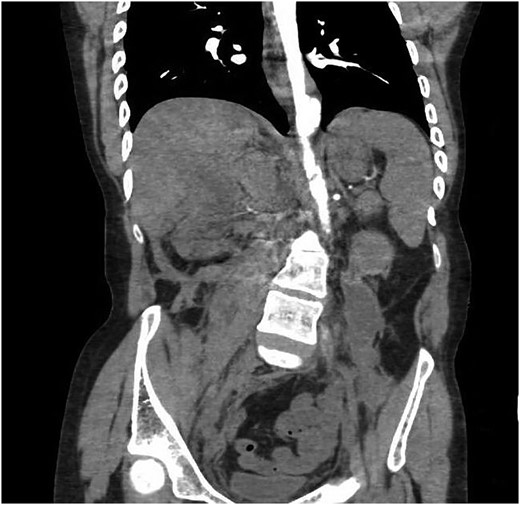

The patient returned to the hospital less than a week later in extremis. He had severe back pain and was diaphoretic. The patient was hypotensive and tachycardiac. He had no femoral pulses. Repeat CT scan revealed extension of the aortic injury in the abdominal aorta with no flow in the iliac (Figs 2–4). The patient was emergently taken to the operating room (OR) where the aorta, iliac and femoral vessels were unable to hold sutures. We were unable to repair this patient's aorta. Post-operatively, we spoke with the family, and the patient was allowed to expire.

Note contrast in the distal aorta but no contrast in the iliac arteries.